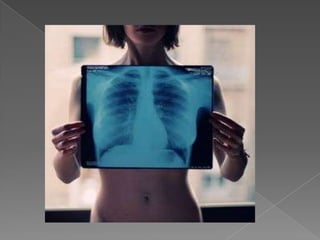

ПРИЛОЖЕНИЕ В МЕДИЦИНАТАРентгеновителъчи се използват в медицината от 1895 и сапървият вид радиация, с помощта на която е наблюдаванавътрешността на човешкототяло. Рентгеновителъчипреминаватпрезтъканите на тялото и същопритежаватсвойството да потъмняватфотографскифилм, когатопреминатпрезтях.Различнитеоргани и тъкани на човешкототялопоглъщатрентгеновителъчи в различна степен: например костите и други образования, съдържащикалций, гипоглъщатпо-силно от мекитетъкани, на което се основаваизползването на рентгеновителъчи в медицината за наблюдение на вътрешнитеорганиначовека – кости, бели дробове и др. Изследваната част от тялото се осветява с рентгеновителъчи, които частично се поглъщат от нея, преминалителъчипопадатвърхуфотографскифилм.

ПРИЛОЖЕНИЕ В МЕДИЦИНАТАРентгеновителъчисе използват в медицината от 1895 и сапървият вид радиация, с помощта на която е наблюдаванавътрешността на човешкототяло. Рентгеновителъчипреминаватпрезтъканите на тялото и същопритежаватсвойството да потъмняватфотографскифилм, когатопреминатпрезтях.Различнитеоргани и тъкани на човешкототялопоглъщатрентгеновителъчи в различна степен: например костите и други образования, съдържащикалций, гипоглъщатпо-силно от мекитетъкани, на което се основаваизползването на рентгеновителъчи в медицината за наблюдение на вътрешнитеорганиначовека – кости, бели дробове и др. Изследваната част от тялото се осветява с рентгеновителъчи, които частично се поглъщат от нея, преминалителъчипопадатвърхуфотографскифилм.